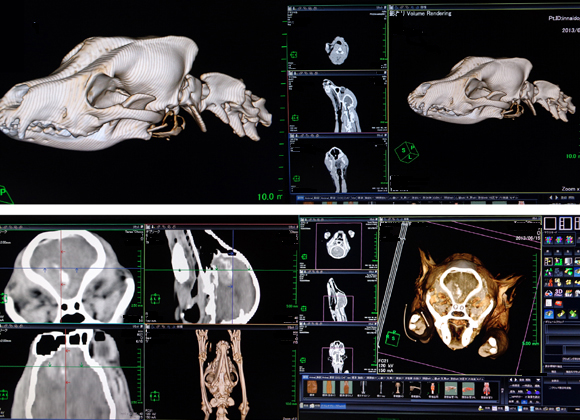

三鷹獣医科グループでは、2013年の4月よりマルチスライス16列CTスキャンを導入しております。これにより高画質、低被爆の条件を満たす院内でのCT検査が可能となりました。これはマルチスライス16列CTシステム「Activion™ 16」を新たに動物用に調整し導入したものです。

この導入機は画期的な0.5mmスライス厚データ収集及び3D作成ができ、被爆低減機能などの高級機スペックを備え、骨抜き機能搭載、血管の末梢まで正確に残った状態で3D画像を作成できる東芝の新デザイン機種です。

新型マルチスライスCTシステム「ActivionTM 16」を新たに動物用に調整し導入しました。これは高画質でありながら、低被爆の条件を満たします。この新デザインの東芝の「ActivionTM 16」は画期的な0.5mmスライス厚データ収集及び、易しく3D作成ができ、被爆、低減機能などの高級機スペックを備えた、骨抜き機能を搭載、血管の末梢まで正確に残った状態で3D画像を作成できます。また、形状認識機能を装備していますので、骨のみを的確に削除でき最先端のアプリケーションを駆使したCT検査が動物の最先端医療の応用にますます身近なものになります。